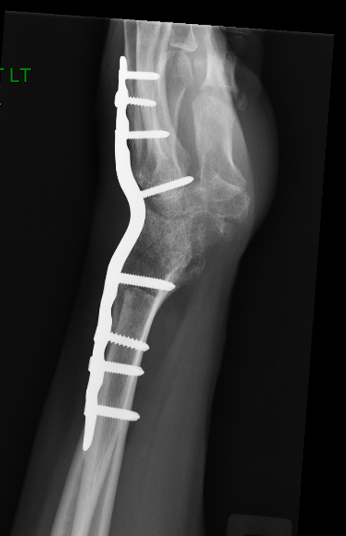

After your hand and wrist has been examined, an X-ray usually determines the degree of damage to the wrist. However, as is often the case, the findings on the X-ray may not correlate with the findings on examination. Some patients may have severe arthritis on their X-ray, yet have very mild symptoms.

X-rays normally show a gap between the bones, as the bones are lined with smooth cartilage, which doesn’t show up on an X-ray. If the cartilage is reduced or absent, the gap between the bones is also reduced, and the ends of bones rub against each other. The body tries to react by making more bone at the edges of the joint. Within the wrist joint, inflammation may develop and this may be painful.

Fusion operations: Fusion is the term given whereby the joint is removed and the bones either side are pinned and held together, so that the bones heal as one piece. The wrist can be partially or fully fused. These operations sacrifice movement of the wrist for pain relief. This is usually the most reliable and predictable treatment for intractable wrist arthritis with up to 85% satisfaction.